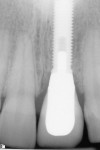

Case 1: One of the worst scenarios is an implant that is facially placed and too shallow. In Case 1, there were several factors to consider—how far facially the implant was, the diameter of the implant, and the depth of its placement. The implant was actually placed too deep (Figure 1), however this would allow for some correction. The abutment and facial emergence profile should be flat and almost concave. In this case the implant crown had been replaced and the emergence profile was kept very flat (Figure 2). The patient was informed that the ideal treatment would be explantation, grafting, and implant replacement. However, the patient refused that plan, and accepted the fact that an ideal correction in the gingival levels would not be possible.